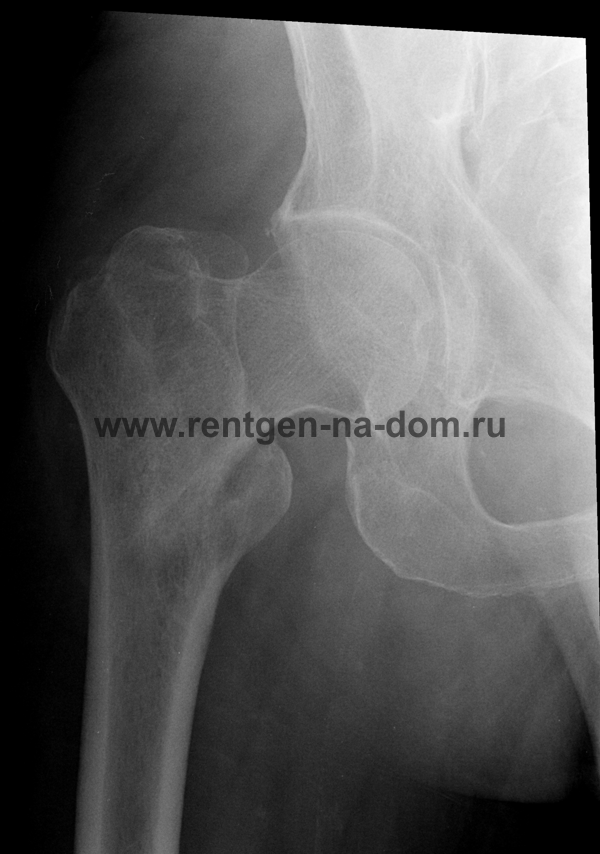

Перелом шейки бедренной кости.

- субкапитаьный, трансцервикальный и базисцервикальный переломы бедренной кости, относящихся к группе медиальных переломов

- чрезвертельный и подвертельный переломы бедренной кости,относящися к группе латеральных переломов

Решающее значение в установлении диагноза перелома шейки бедра имеет рентгенография тазобедренного сустава. У пожилых пациентов приведенные выше симптомы могут проявляться нечетко, а такие заболевания как инсульт или невропатия, вообще, не позволят поставить правильный диагноз без рентгена. Где сделать рентген? Перелом шейки бедра всегда сопровождается сильной болью, поэтому любые лишние движения оборачиваются новыми мучениями, а сопутствующие заболевания внутренних органов усугубляют ситуацию! Решение есть - воспользоваться уникальной услугой – цифровой рентген на дому. К вам приедет врач рентгенолог-травматолог, который выполнит весь комплекс лечебно-диагностических мероприятий и подробно расскажет, что делать дальше.